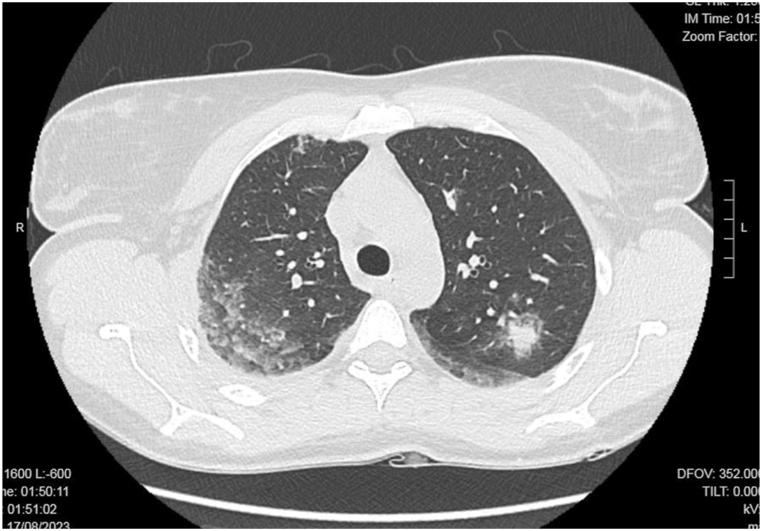

We report the case of a 34-year-old previously healthy female who developed acute respiratory failure after completing a prophylactic regimen of mefloquine for malaria prevention. The patient initially presented with fever, dyspnea, and hypoxemia, rapidly progressing to severe respiratory distress requiring invasive mechanical ventilation. Laboratory tests revealed marked eosinophilia, while thoracic computed tomography (CT) demonstrated diffuse ground-glass opacities and nodular infiltrates. Bronchoalveolar lavage (BAL) was positive for Rhinovirus, suggesting a possible interplay between drug-induced hypersensitivity and viral infection. Following corticosteroid therapy and supportive care, the patient's condition improved, with resolution of eosinophilia and radiological abnormalities.

我们报告一例34岁既往健康的女性,在完成预防疟疾的甲氟喹预防方案后发生急性呼吸衰竭。患者最初表现为发热、呼吸困难和低氧血症,迅速进展为严重呼吸窘迫,需要有创机械通气。实验室检查显示明显的嗜酸性粒细胞增多,而胸部计算机断层扫描(CT)显示弥漫性磨玻璃影和结节状浸润。支气管肺泡灌洗(BAL)检测出鼻病毒阳性,提示药物性超敏反应与病毒感染之间可能存在相互作用。经过糖皮质激素治疗和支持治疗,患者病情改善,嗜酸性粒细胞增多和影像学异常消失。